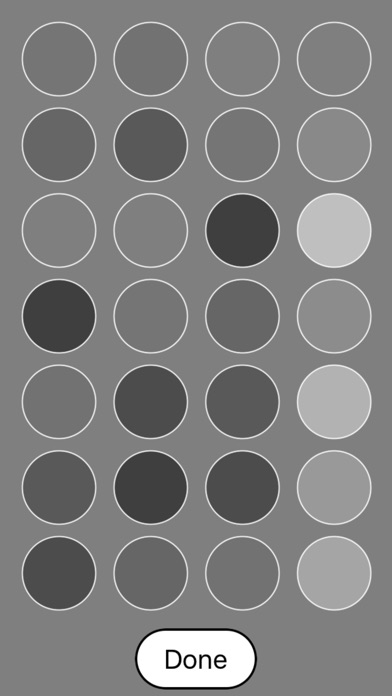

eyeFusion is an application to measure your flicker fusion threshold (also referred to as visual conductance or flicker sensitivity) through self-testing.